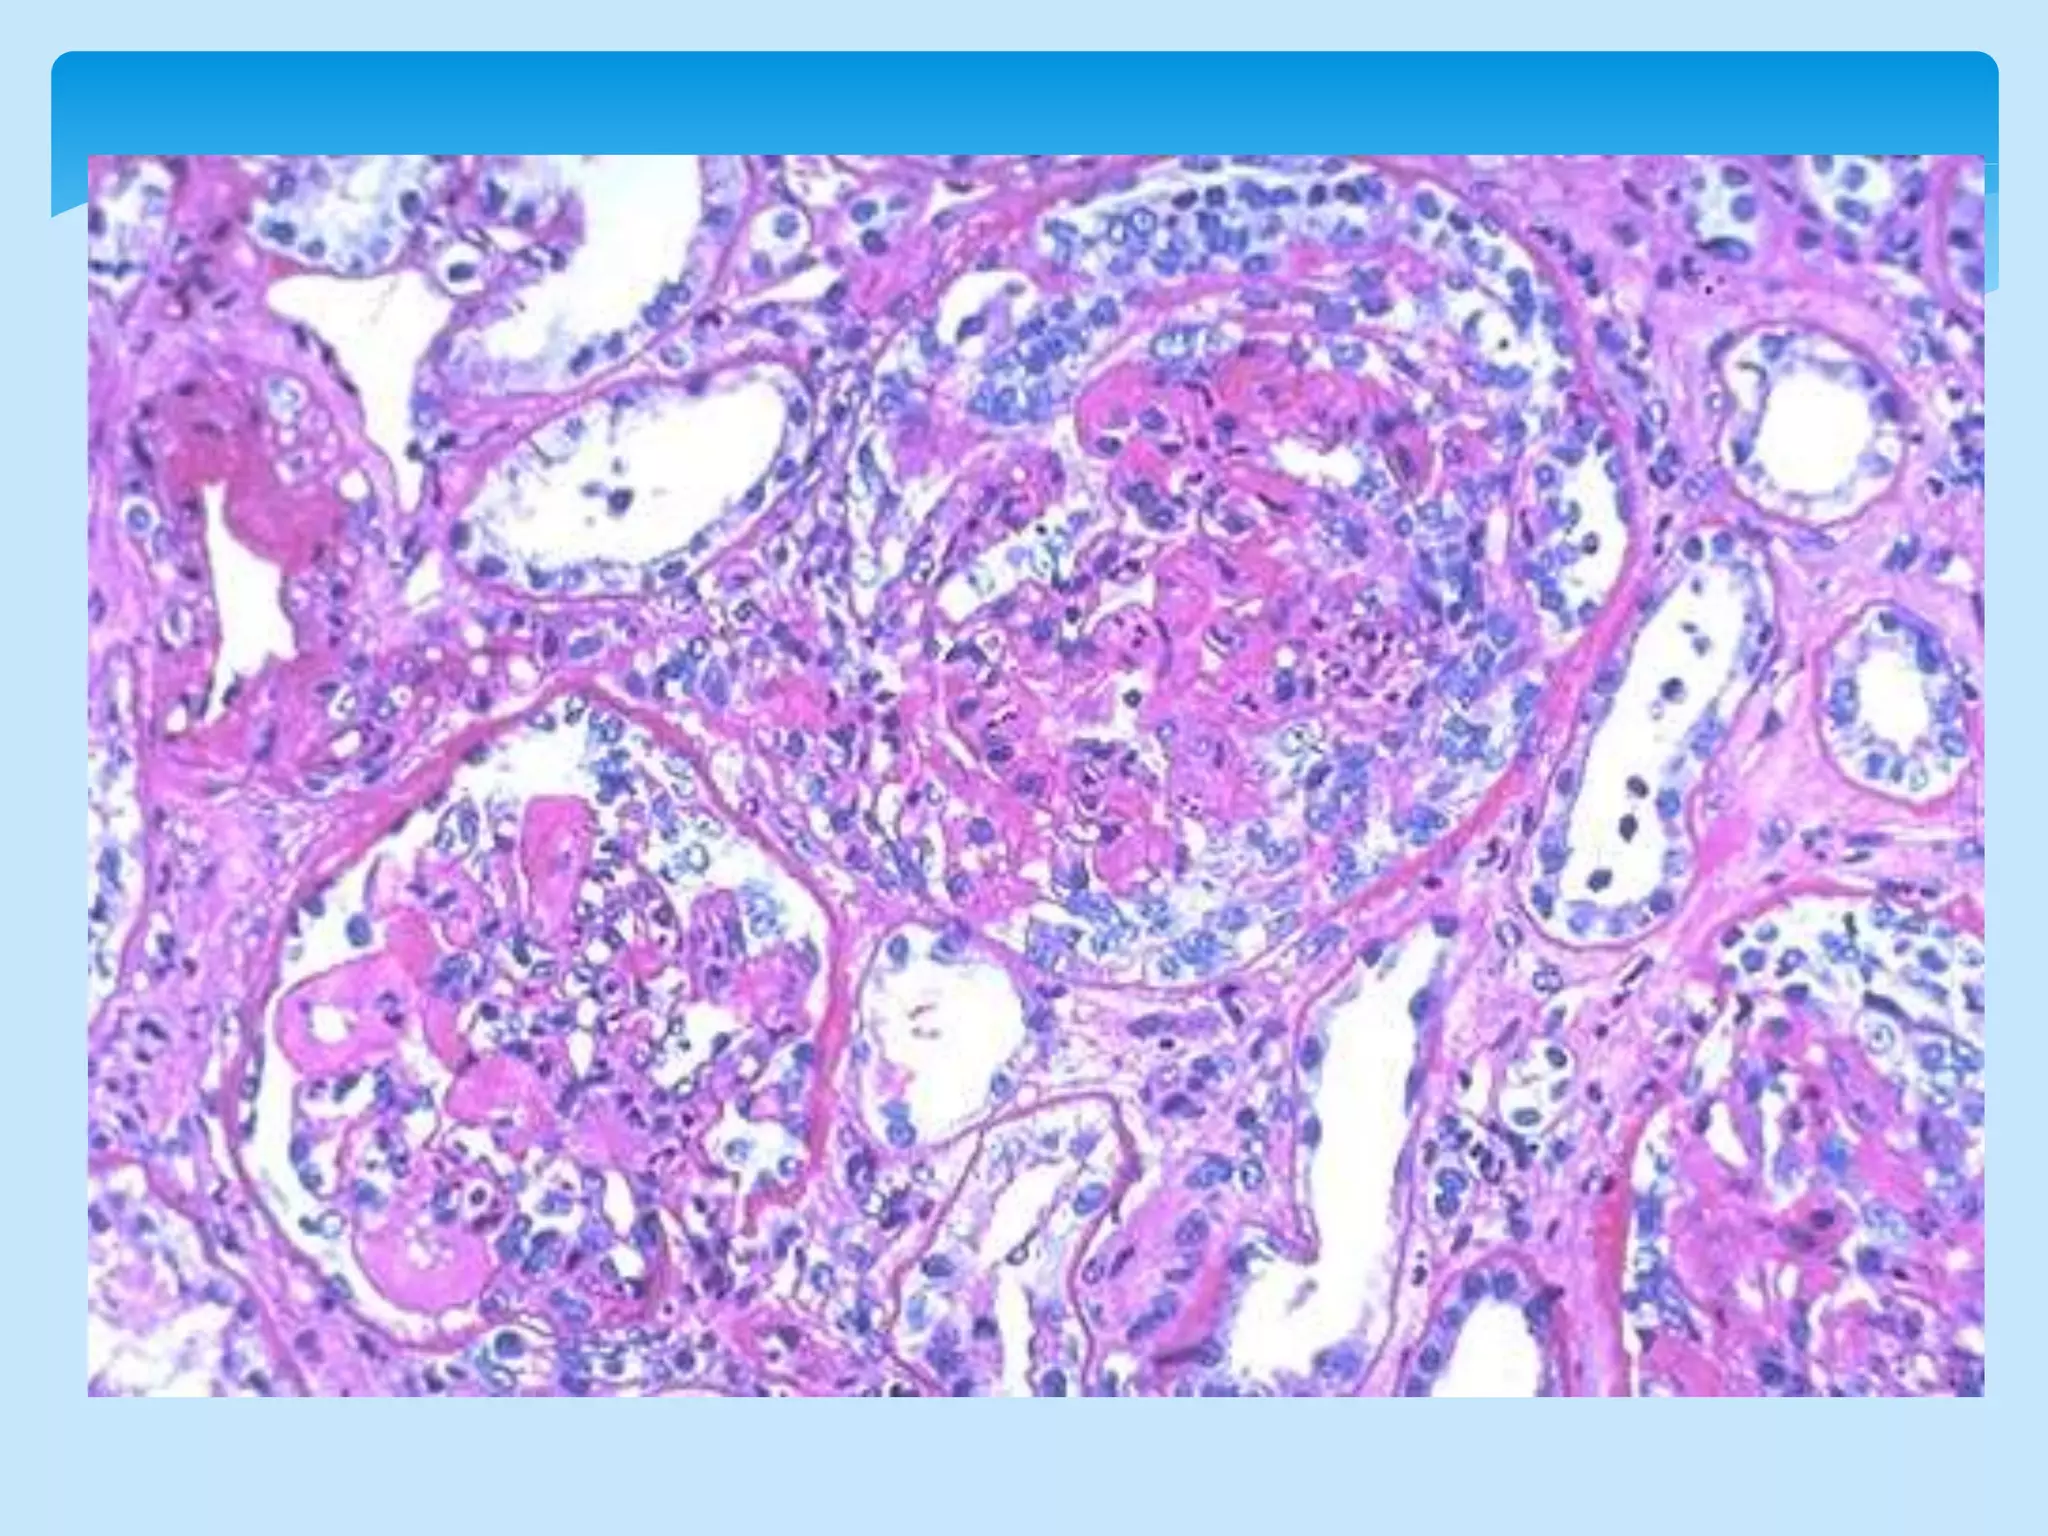

 Light Microscopy-

 37% have focal proliferative glomerulonephritis,28% have DPGN

 Wide spread damage can present lupus like.

MICROSCOPY:

• Subendothelial dep. and mesangial hypercellularity are chief picture a/w

endocapillary thickening,global capillary wall thickening leading to picture of

HYPERSEGMENTATION AND LOBULATION.

• Tram track appearence on methanamine silver staining.